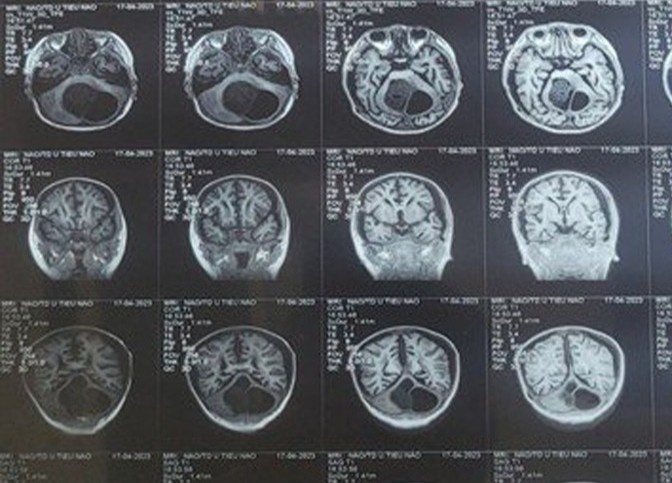

Bệnh nhân trên cần chụp MRI để kiểm tra có bất kỳ u nang nào trong não hay không. Nếu tồn tại ở vị trí đó, các u nang do ký sinh trùng để lại có thể gây ra nguy hại cho sức khỏe.